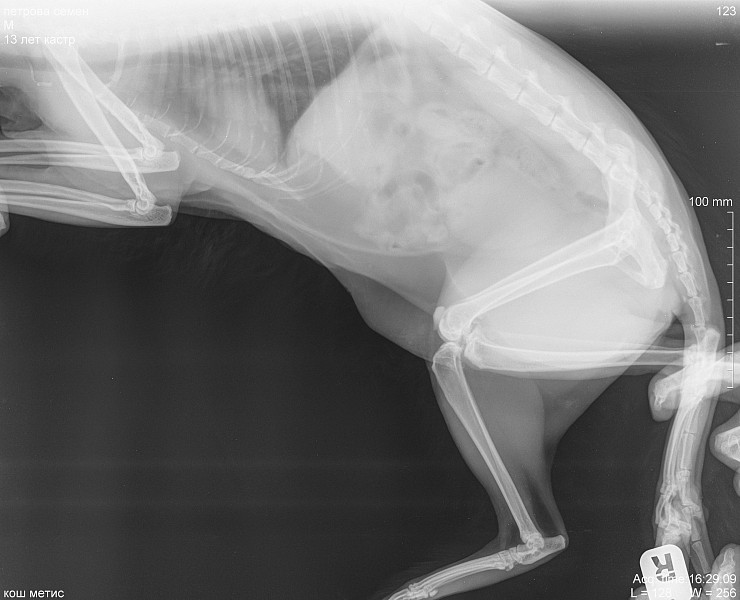

Рентген Задней Лапы Кошки: Нормы и Диагностика